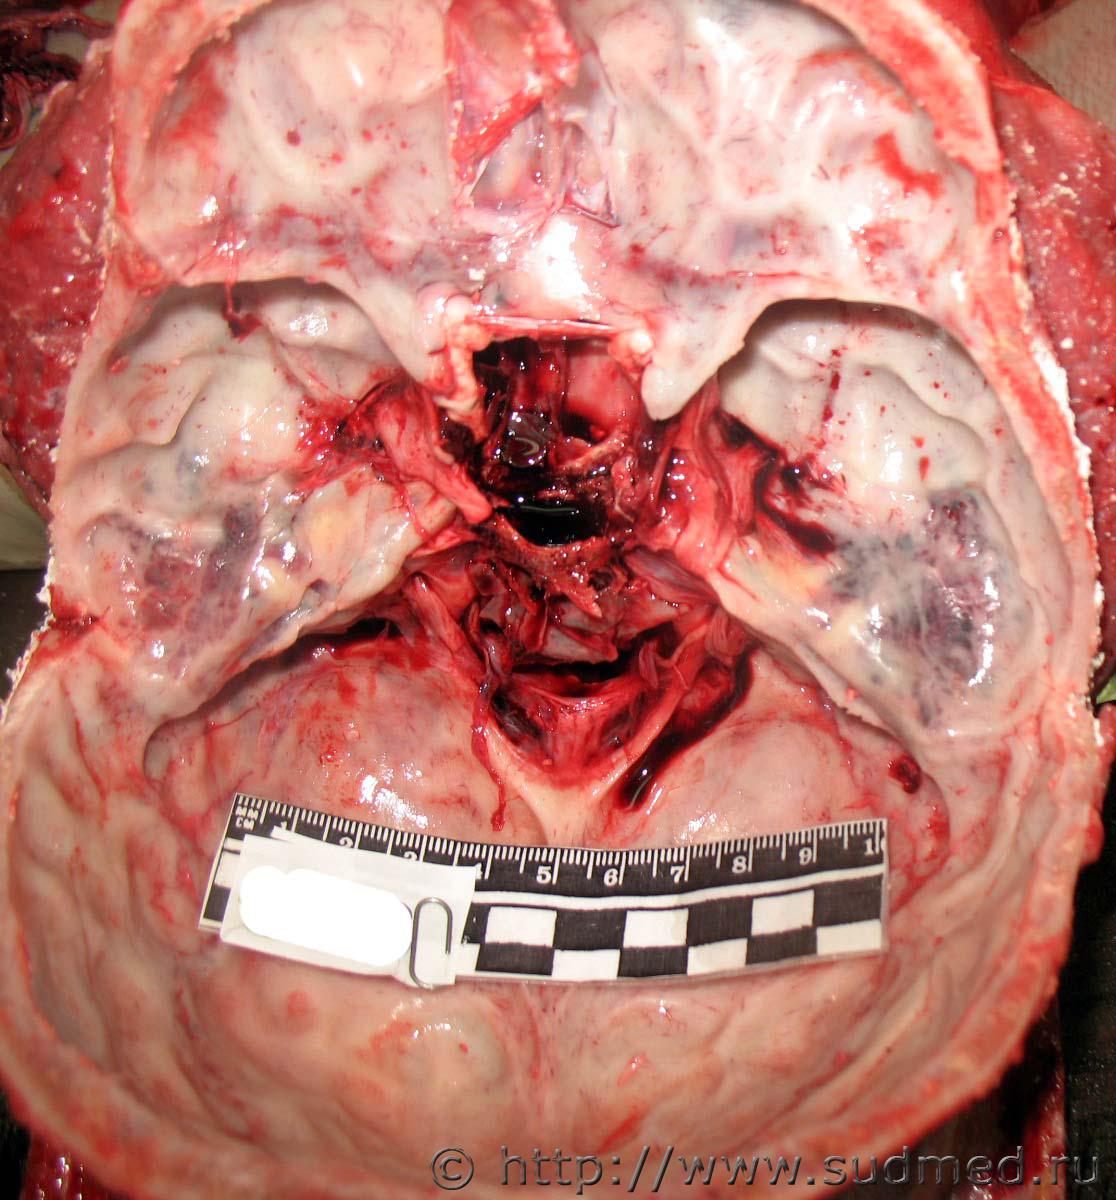

В чешуе затылочной кости - дырчатый перелом, общий вид снаружи Судебная медицина - Прикрепленное изображение, детальный вид с наружной Судебная медицина - Прикрепленное изображение и внутренней Судебная медицина - Прикрепленное изображение костных пластинок.

Из чешуи лобной кости выступал конический конец металлического инородного предмета Судебная медицина - Прикрепленное изображение Судебная медицина - Прикрепленное изображение.

После вскрытия полости черепа предмет идентифицирован Судебная медицина - Прикрепленное изображение.

Вид снаружи дырчатого перелома в чешуе лобной кости Судебная медицина - Прикрепленное изображение Судебная медицина - Прикрепленное изображение.

Вид со стороны полости черепа повреждений костей его основания Судебная медицина - Прикрепленное изображение.

Снаряд - металлический дюбель Судебная медицина - Прикрепленное изображение.

Остальные части трупа не обнаружены, личность не идентифицирована.